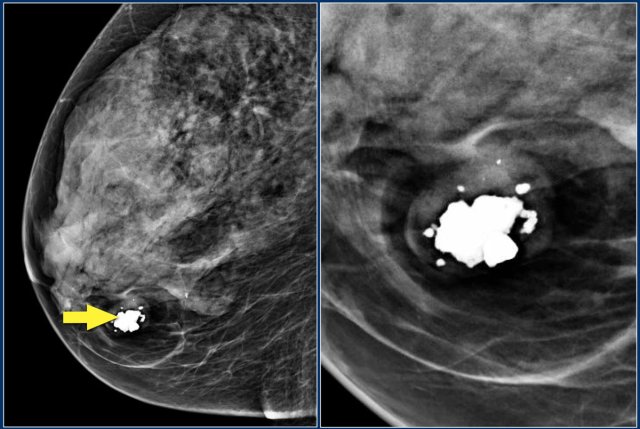

- Spiculated, irregular highdensity mass.

- Segmental or linear arrangement of fine linear calcifications.

- Irregular spiculated mass with associated pleomorphic calcifications.

First study the images and describe the findings.

Then continue reading.

The findings are:

- Mass with irregular shape.

- Spiculated margin.

- High density.

- Ultrasound also shows irregular shape with indistinct margin.

This mass is categorized as BI-RADS 5.

BI-RADS 5

DO

- Use if a combination of highly suspicious findings are present:

- Spiculated, irregular mass + high-density.

- Fine linear calcifications + segmental or linear arrangement .

- Irregular spiculated mass + associated pleomorphic calcifications.

- Use in findings for which any nonmalignant percutaneous tissue diagnosis is automatically considered discordant